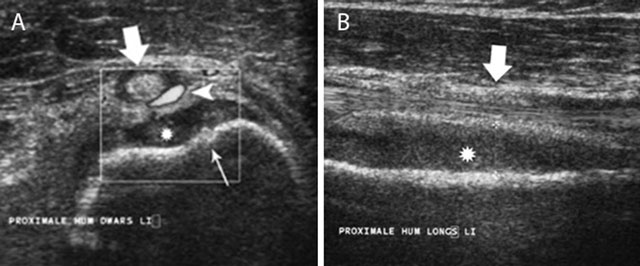

Figure 6

Acute childhood osteomyelitis of the proximal humerus on ultrasound. Transverse (a) and longitudinal (b) ultrasound images of the proximal humerus. Note focal thinning of the humeral cortex (thin white arrow) on the axial images in keeping with a cortical penetration of the infection causing subperiosteal pus collection (asterisk). There is also increased Doppler signal (white arrow head) within the synovium of the long head of the biceps tendon (large white arrow).

Ultrasound (US) allows easy comparison of both sides. It is an accurate and quick tool to detect subperiosteal spread in acute OM particularly in children because of loose attachment of the periosteum. Visualization of periosteal elevation, fluid collections or abscesses are signs suggestive of osteomyelitis. A soft tissue abscess presents as a hypo-echogenic collection to normal muscle with a peripheral vascularized rim of increased Power Doppler signal. US detects these signs earlier than standard radiography and allows US-guided biopsy and/or aspiration (Figure 6) [7].